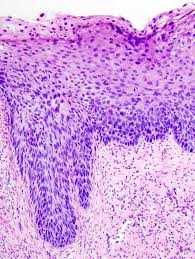

Mesothelioma Histology Usmle : Asbestosis And Silicosis Causes And Treatments Medical Library / Mesothelioma histology is the study of the function and structure of anatomy, including tissues and cells.. Histology isn't historically the most high yield topic on the boards, but the questions that have a histology image included can be easy points if you take a step back, don't freak out. Histology also helps avoid misdiagnosis of mesothelioma. Generally mesothelioma is an aggressive and deadly form of cancer. Mesothelioma videos, flashcards, high yield notes, & practice questions. Malignant mesothelioma treatment may include surgery, radiation therapy, and chemotherapy.

Quickly memorize the terms, phrases and much more. Mesothelioma histology includes the study of cancerous mesothelioma cells. Our mesothelioma course covers all essentials: Histology, or histopathology, is essential to define cancer cells at their most basic level. The histology of mesothelioma can provide insight to those who have been or have loved ones diagnosed with this cancer.

Malignant mesothelioma treatment may include surgery, radiation therapy, and chemotherapy. Malignant pleural mesothelioma is an aggressive cancer with poor prognosis, linked to vascular endothelial growth factor is a key mitogen for malignant pleural mesothelioma cells. Many mesothelioma specialists favor histology over any other form of diagnosis, including cytology, because it's the most. Mesothelioma is a type of cancer that develops from the thin layer of tissue that covers many of the internal organs (known as the mesothelium). Like any other cancer issues. Quickly memorize the terms, phrases and much more. Peritoneal mesothelioma and ovarian cancer, for example. Cell biology, histology, general pathology at cram.com. Mesothelioma is difficult to diagnose by examining the macrostructure of the tumor. Histology also helps avoid misdiagnosis of mesothelioma. Tumor markers, from first aid for the usmle step 1 learn with flashcards, games and more — for free. Mesothelioma is a rare form of cancer in which malignant (cancerous) cells are found in the mesothelium most people who develop mesothelioma have worked on jobs where they inhaled asbestos particles. Other risk factors for mesothelioma include exposure to thorotrast and repeated mesothelial irritation.

Histology also helps prevent mesothelioma misdiagnosis. Mesothelioma's histology reveals epithelial and sarcomatoid cell types. Germline bap1 mutation has been associated with early onset and less. Pathologists examine macrostructures, but also microscopic structures like cells. Histology isn't historically the most high yield topic on the boards, but the questions that have a histology image included can be easy points if you take a step back, don't freak out.

Usmle Step 1 High Yield Free Download Borrow And Streaming Internet Archive from archive.org Mesothelioma is a malignancy involving mesothelial cells that line the body cavities, including the pleura, peritoneum, pericardium, and testis. Many mesothelioma specialists favor histology over any other form of diagnosis, including cytology, because it's the most. Analyzing the cell type helps doctors tell the difference. Generally mesothelioma is an aggressive and deadly form of cancer. Quickly memorize the terms, phrases and much more. An important tool used in the definitive diagnosis of disease is histology, the microscopic examination of cellular anatomy. Histology also helps avoid misdiagnosis of mesothelioma. Cell biology, histology, general pathology at cram.com.

Mesothelioma's histology reveals epithelial and sarcomatoid cell types. Mesothelioma treatments are available, but for many people with mesothelioma, a cure isn't possible. Mesothelioma most often develops in the lining of the lungs and pleural cavity, and is well known for its association with. Histology, or histopathology, is essential to define cancer cells at their most basic level. Histology also helps prevent mesothelioma misdiagnosis. Cram.com makes it easy to get the grade you want! Histology also helps avoid misdiagnosis of mesothelioma. Mesothelioma histology includes the study of cancerous mesothelioma cells. Histology isn't historically the most high yield topic on the boards, but the questions that have a histology image included can be easy points if you take a step back, don't freak out. Other risk factors for mesothelioma include exposure to thorotrast and repeated mesothelial irritation. The histology of mesothelioma can provide insight to those who have been or have loved ones diagnosed with this cancer. Learn more from shrader & associates l.l.p. Like any other cancer issues.

Mesothelioma videos, flashcards, high yield notes, & practice questions. Germline bap1 mutation has been associated with early onset and less. Mesothelioma histology is the study of mesothelioma cell types. Cell biology, histology, general pathology at cram.com. Many mesothelioma specialists favor histology over any other form of diagnosis, including cytology, because it's the most. Analyzing the cell type helps doctors tell the difference. Mesothelioma is a rare form of cancer in which malignant (cancerous) cells are found in the mesothelium most people who develop mesothelioma have worked on jobs where they inhaled asbestos particles. Peritoneal mesothelioma and ovarian cancer, for example. Other risk factors for mesothelioma include exposure to thorotrast and repeated mesothelial irritation. For example, peritoneal mesothelioma and ovarian cancer can be difficult to differentiate. Pathologists examine macrostructures, but also microscopic structures like cells. Mesothelioma is a type of cancer that develops from the thin layer of tissue that covers many of the internal organs (known as the mesothelium). Histological analysis of malignant tissue is an invaluable tool in diagnosing a patient's mesothelioma, as well as monitoring.